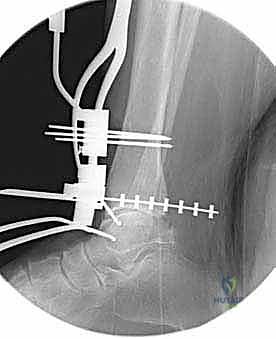

4. وضع أدلة القطع (Jig Placement and Alignment)

تعتمد دقة الجراحة على المحاذاة الصحيحة. يتم استخدام أجهزة توجيه متطورة (Jigs) تثبت على عظمة الساق باستخدام دبابيس معدنية. يتم التحقق من صحة الزوايا والمحاور باستخدام جهاز الأشعة السينية المباشر داخل غرفة العمليات (C-arm Fluoroscopy). يضمن الدكتور هطيف أن يكون القطع موازياً للأرض تماماً عند وقوف المريض.

5. القطع العظمي الظنبوبي (Tibial Bone Cut)

باستخدام منشار جراحي دقيق التذبذب، يتم إزالة شريحة رقيقة جداً (بضعة مليمترات) من السطح السفلي التالف لعظمة الظنبوب. يتم القطع بحذر شديد لتجنب إصابة الأوتار الخلفية أو الأوعية الدموية.

6. القطع العظمي الكاحلي (Talar Bone Cut)